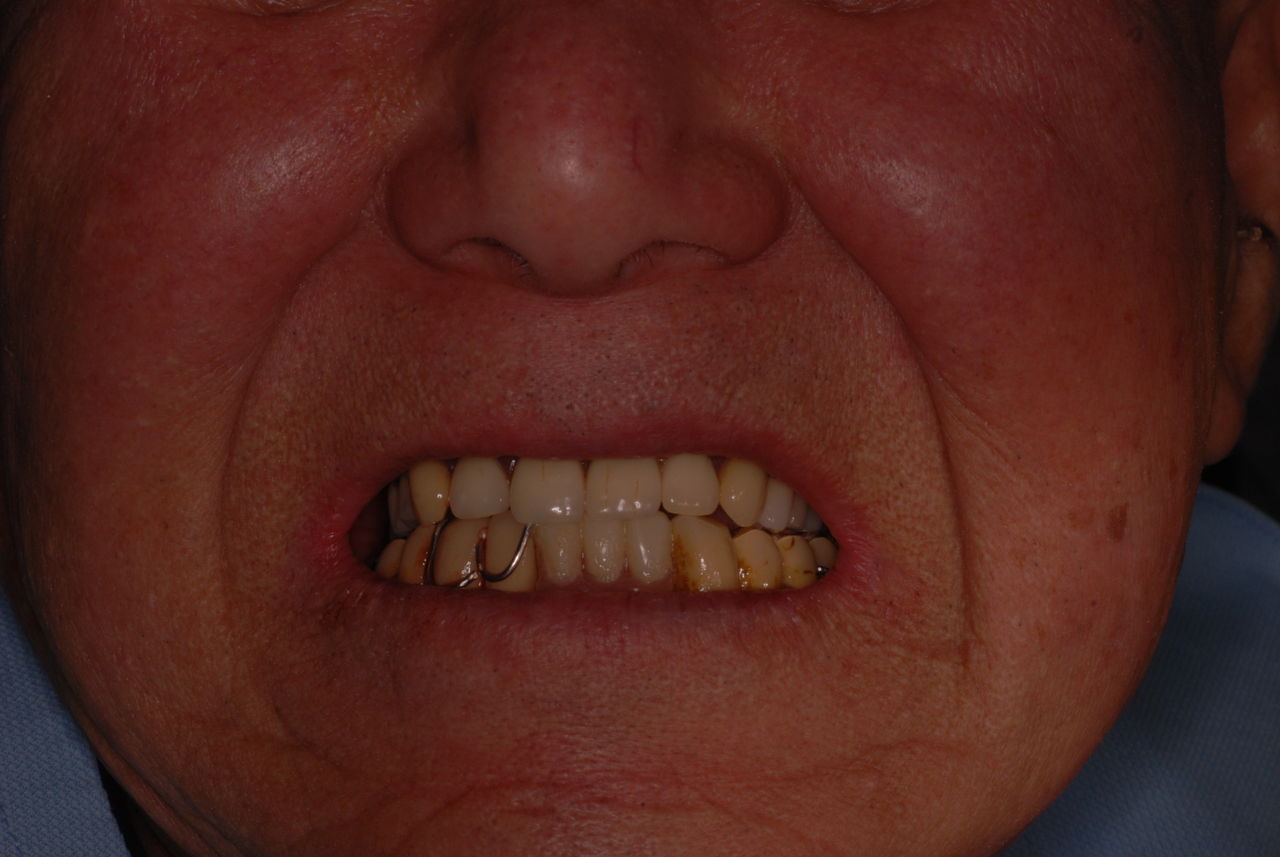

84歳になる方ですが娘さんから電話がありましたのは12月13日、そして1月3日のお囃子で笛を吹きたいから大急ぎで噛める、そして吹ける入れ歯を作って欲しいという要望でした。

無理だとは思いましたが12月15日に来ていただき唖然とした次第です。

金属にもかかわらず適合が悪い為にプラスチックを重ね着した為に厚くなりしゃべりにくくなっていました。

かなり分厚い入れ歯です。